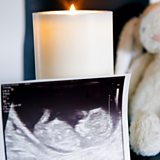

Tommy's charity campaign, calls for a nationwide rollout of its 'Graded Model of Miscarriage Care', which offers support when a family experiences their first pregnancy loss.